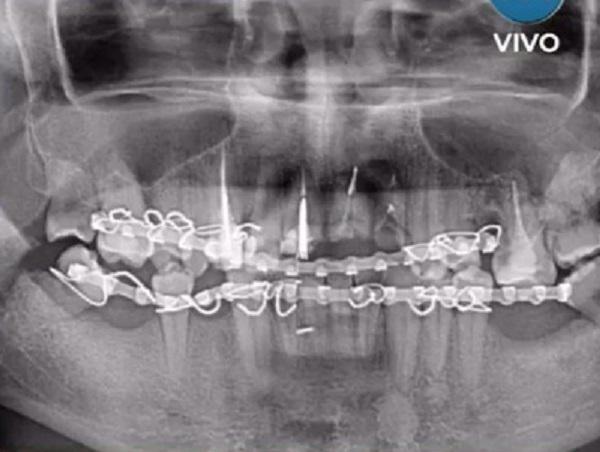

El hombre sufrió desplazamiento de mandíbula y espera una prótesis. En tanto no puede comer y su situación es complicada. Ante este hecho la familia medina pidió justicia por Emiliano pero lo cierto es que hasta el momento lo único que obtuvieron fue una carátula como lesiones leves y los 10 agresores que conforman esta patota siguen libres y haciendo de las suyas.

Según Multivisión el caso tendría que estar bajo la Fiscalía Penal de Cerrillos o a la localidad de El Carril, a la cual la familia cuestiona su intervención.